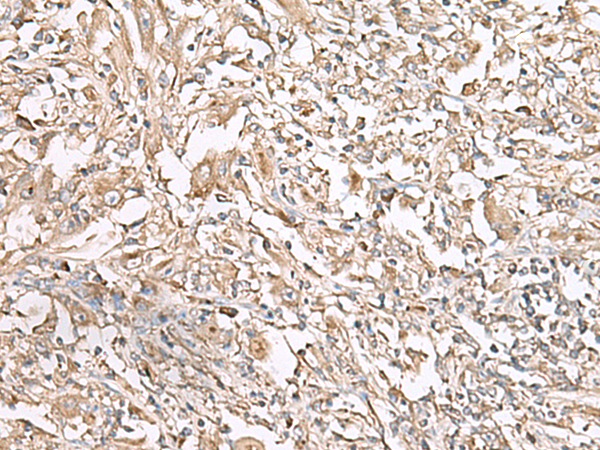

分类: 科研抗体货号: P11628别名: LEC; LMC; NCC4; CKb12; HCC-4; LCC-1; Mtn-1; NCC-4; SCYL4; ILINCK; SCYA16应用: WB,IHC反应种属: Human